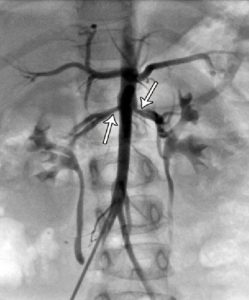

ایسکمی حاد اندام (ALI) یک اورژانس عروقی است که در آن خونرسانی شریانی به یک یا چند اندام به شدت کاهش مییابد. ترومبوز شریانی و آمبولی قلب مسئول اکثر موارد هستند. علائم و نشانههای معمول شامل درد، رنگ پریدگی، کاهش نبض، سردی، فلج و پارستزی اندام است که در قسمت دیستال به محل انسداد ایجاد میشود.